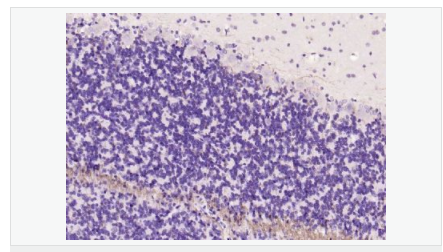

| 產(chǎn)品應(yīng)用 | WB=1:500-2000 ELISA=1:5000-10000 IHC-P=1:100-500 IHC-F=1:100-500 Flow-Cyt=1ug/test IF=1:100-500 (石蠟切片需做抗原修復(fù)) not yet tested in other applications. optimal dilutions/concentrations should be determined by the end user. |

| 產(chǎn)品介紹 | The classic group of Myelin basic protein (MBP) isoforms (isoforms 4 to 14) are with PLP the most abundant protein components of the myelin membrane in the CNS. They have a role in both its formation and stabilization. The smaller isoforms might have an important role in remyelination of denuded axons in multiple sclerosis. The non classic group of MBP isoforms (isoforms 1 to 3/Golli MBPs) may preferentially have a role in the early developing brain long before myelination, maybe as components of transcriptional complexes, and may also be involved in signaling pathways in T cells and neural cells. Differential splicing events combined to optional posttranslational modifications give a wide spectrum of isomers, each of them having maybe a specialized function. Function: The classic group of MBP isoforms (isoform 4-isoform 14) are with PLP the most abundant protein components of the myelin membrane in the CNS. They have a role in both its formation and stabilization. The smaller isoforms might have an important role in remyelination of denuded axons in multiple sclerosis. The non-classic group of MBP isoforms (isoform 1-isoform 3/Golli-MBPs) may preferentially have a role in the early developing brain long before myelination, maybe as components of transcriptional complexes, and may also be involved in signaling pathways in T-cells and neural cells. Differential splicing events combined with optional post-translational modifications give a wide spectrum of isomers, with each of them potentially having a specialized function. Induces T-cell proliferation. Subunit: Homodimer. Isoform 3 exists as a homodimer. Subcellular Location: Myelin membrane; Peripheral membrane protein; Cytoplasmic side. Note=Cytoplasmic side of myelin. Tissue Specificity: MBP isoforms are found in both the central and the peripheral nervous system, whereas Golli-MBP isoforms are expressed in fetal thymus, spleen and spinal cord, as well as in cell lines derived from the immune system. Post-translational modifications: Several charge isomers of MBP; C1 (the most cationic, least modified, and most abundant form), C2, C3, C4, C5, C6, C7, C8-A and C8-B (the least cationic form); are produced as a result of optional PTM, such as phosphorylation, deamidation of glutamine or asparagine, arginine citrullination and methylation. C8-A and C8-B contain each two mass isoforms termed C8-A(H), C8-A(L), C8-B(H) and C8-B(L), (H) standing for higher and (L) for lower molecular weight. C3, C4 and C5 are phosphorylated. The ratio of methylated arginine residues decreases during aging, making the protein more cationic. The N-terminal alanine is acetylated (isoform 3, isoform 4, isoform 5 and isoform 6). Arg-241 was found to be 6% monomethylated and 60% symmetrically dimethylated. Phosphorylated by TAOK2, VRK2, MAPK11, MAPK12, MAPK14 and MINK1. Similarity: Belongs to the myelin basic protein family. SWISS: N/A Gene ID: 100731253 Database links: Gene ID: 100731253 Guinea pig Entrez Gene: 4155 Human Entrez Gene: 17196 Mouse Omim: 159430 Human SwissProt: P02686 Human SwissProt: P04370 Mouse SwissProt: P25274 Rabbit Unigene: 551713 Human Unigene: 63285 Rat Important Note: This product as supplied is intended for research use only, not for use in human, therapeutic or diagnostic applications. 神經(jīng)生物學(xué)相關(guān)蛋白(Neurobiology) 少突膠質(zhì)細(xì)胞標(biāo)志物 主要用于脊髓脫髓鞘病-脊髓多發(fā)硬化癥的研究。 MBP髓鞘堿性蛋白和髓鞘相伴糖蛋白是多發(fā)性硬化的自身免疫攻擊的靶。 Myelin basic protein (MPB) :Oligodendrocyte Protein produced by mature oligodendrocytes; located in the myelin sheath surrounding neuronal structures 髓磷脂Myelin/oligodendrocyte specific protein (MOSP)是由中樞神經(jīng)系統(tǒng)中少突膠質(zhì)細(xì)胞和外周神經(jīng)系統(tǒng)中雪旺氏細(xì)胞產(chǎn)生特殊蛋白質(zhì)。是形成髓鞘的主要成分,對于引導(dǎo)神經(jīng)沖動的傳遞起著致關(guān)重要的作用。 多年來,關(guān)于髓鞘的形成機(jī)理和與其相關(guān)的一些先天性疾病的發(fā)病機(jī)制一直是眾多科學(xué)家關(guān)注的重點(diǎn)。如:多重硬化癥和腦白質(zhì)營養(yǎng)不良等,都與神經(jīng)系統(tǒng)的去髓鞘化相關(guān)。 |